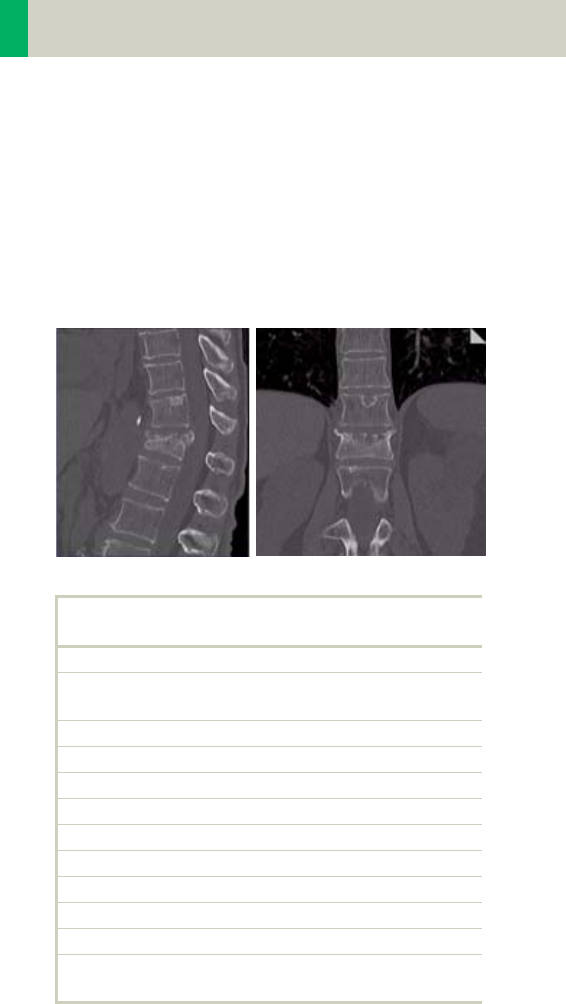

Spine 294

•Overview 294

- General Hints 296

- Body Kernels 297

•Scan Protocols 298

- C-Spine 298

- C-SpineVol 300

- SpineRoutine 302

- SpineThinSlice 304

- SpineVol 305

Contents

11

- SpineSeq 308

- Osteo 312